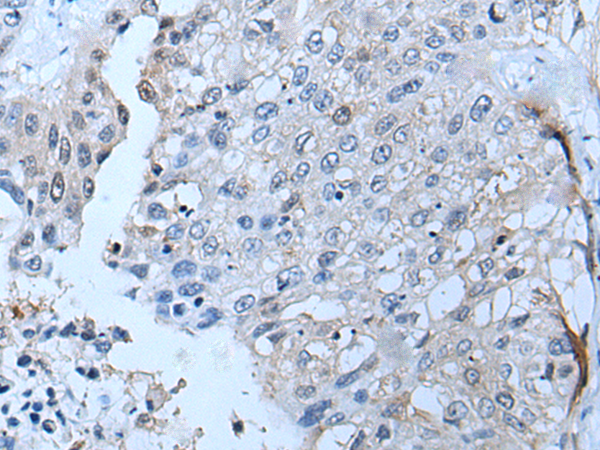

分类: 科研抗体货号: P07218别名: COX11P应用: WB,IHC反应种属: Human, Mouse